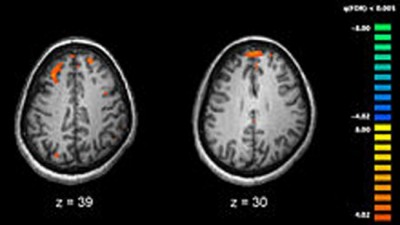

New York, Jan 17 (IBNS): A high-salt diet reduces resting blood flow to the brain and causes dementia in mice, according to a new study by scientists from Weill Cornell Medicine.